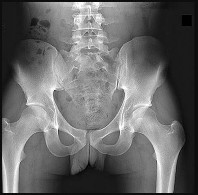

Figures 12a and 12b are a recent radiograph and a whole-body bone scan of an 81-year-old man who has hip pain and difficulty walking. His medical history is significant for obesity, hypertension, chronic kidney disease, and coronary artery disease. An examination demonstrates

moderate tenderness with passive range of motion of the left hip and an inability to actively flex the left hip against gravity. What is the best next step?

This patient has no known history of active malignancy. The radiograph shows a lesser trochanteric avulsion fracture (a fracture routinely associated with an underlying neoplasm). The bone scan reveals no other bone lesions. The femur fracture is statistically most likely to occur because of metastatic disease, but, without other evidence of metastasis, a primary bone sarcoma is possible, and biopsy is recommended before surgical fixation. Observation of this fracture, which is pathognomonic for neoplastic disease, is strongly discouraged.